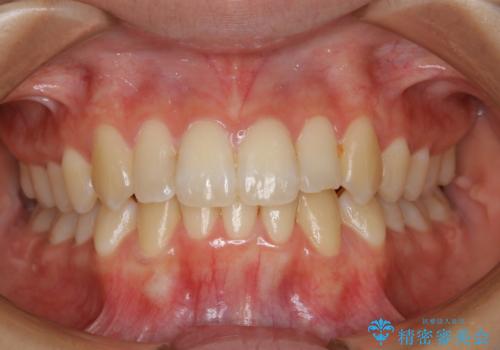

- 上の前歯が1本後ろに入ってしまっていることが気になるとご相談にいらした方です。

元々下の前歯が1本欠損しており、上下の噛み合わせや、歯のサイズバランスを考慮しながら治療を行いました。

クロスバイトしている歯が深く噛み込んでおり、この歯を外に出してくる際に強い咬合力が加わると歯が失活する恐れがあることを説明し、合わせて咬筋へのボトックス注入を行いました。

下顎切歯が1本欠損しているため、上顎前歯部を少しずつストリッピングして、上下の噛み合わせ、バランスの向上を図りました。